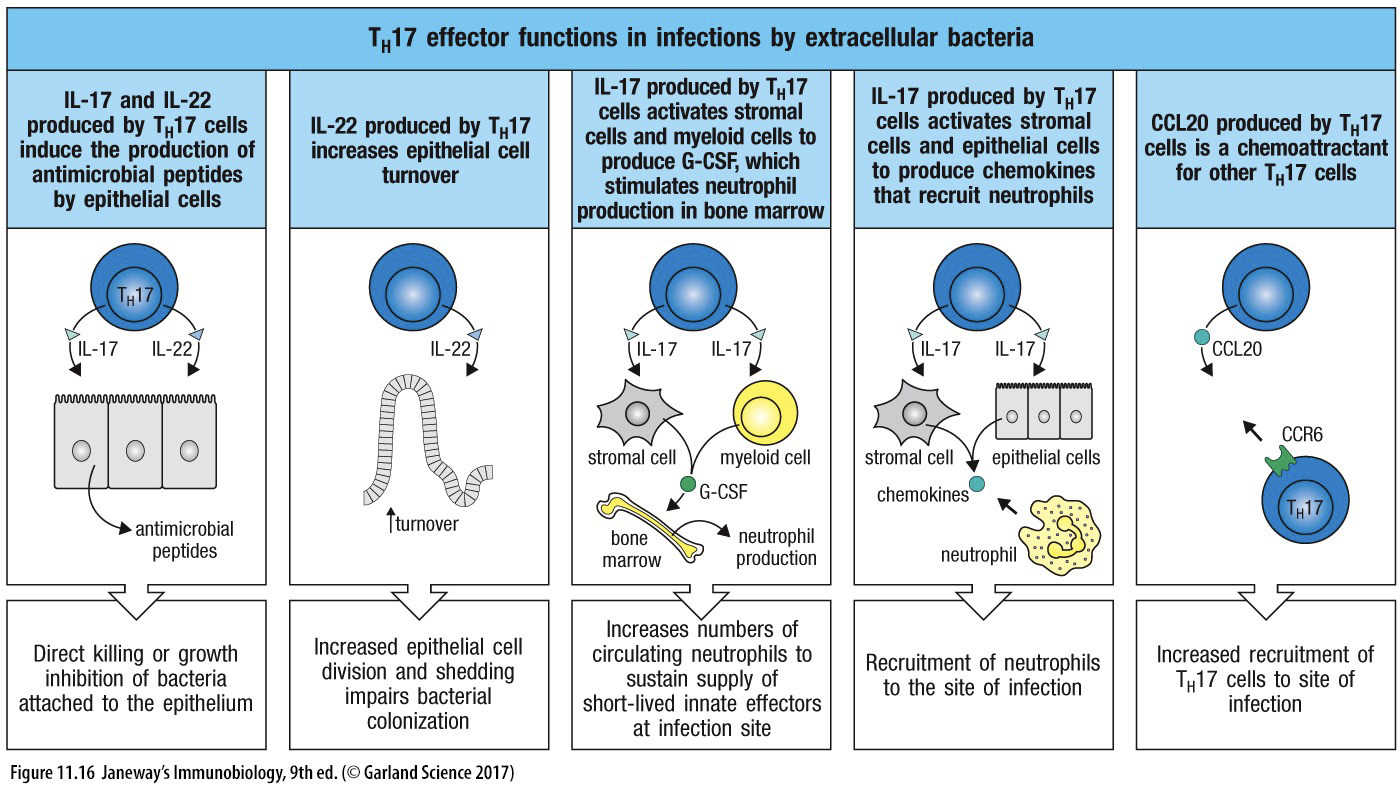

TH17

- 促進 neutrophils 產生

- IL-17

- 骨髓的基質細胞(stromal cell)和髓細胞(myeloid cell)產生G-CSF →嗜中性球(neutrophils)。

- IL-22

- 上皮細胞脫落及再生加速

- IL-17、IL-22 促進上皮細胞產生抗微生物蛋白(antimicrobial peptides)。

- 殺胞外細菌和真菌。

IL-17, 22 (Neutrophils)

- IL-17

- TH17 分泌

- 促進骨髓產 Neutrophils

- 上皮細胞產抗菌蛋白

- IL-22

- TH17 分泌

- 促進上皮更新

- 上皮細胞產抗菌蛋白